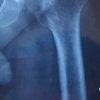

A direct anterior approach (DAA) utilizing an anterior minimally invasive surgery table (Medacta, Castel San Pietro, Switzerland) was performed for the index procedure. Intraoperatively, her abductors appeared intact but moderately atrophic. An in situ femoral neck napkin ring cut was made 1.5 cm proximal to the lesser trochanter. Reaming the acetabulum required advancing through the fused femoral head under live fluoroscopy with the addition of palpation and visual inspection of the acetabular walls. Final implants included a 62 mm multi-hole acetabular shell secured with five screws, a neutral lip liner, and a cementless size 4 femoral stem with a 40 mm standard head (Fig. 3). Intraoperative fluoroscopy showed restoration of leg length and offset, and the hip was stable throughout the arc of ROM. There were no intraoperative or perioperative complications, and she was discharged home weight-bearing as tolerated with anterior hip precautions on post-operative day 2.